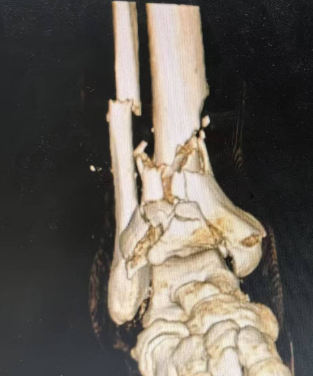

据悉,这位患者是一位壮年男性,因意外创伤导致复杂Pilon骨折,被紧急送往日照市中医医院。入院时,患者患肢肿胀严重,外侧伴有开放创口,骨折部位粉碎且关节面严重受损,治疗难度极大。面对这一棘手病例,创伤中心二病区主任王瑞国手术团队迅速展开全面评估,并制定了个性化的手术方案。

在手术过程中,王瑞国手术团队利用先进的影像学检查技术,精准定位每一处骨折线与碎骨片,为手术提供了详尽的蓝图。随后,团队创新性地采用双反牵引架进行牵引复位,为手术创造了良好的视野和操作空间。在专家的精湛技艺下,碎骨被逐一复位,关节面得到精心重建。最终,内固定钢板与外固定支架的联合应用,如同坚固的桥梁支架,确保了复位后的骨骼在愈合过程中的稳定性。